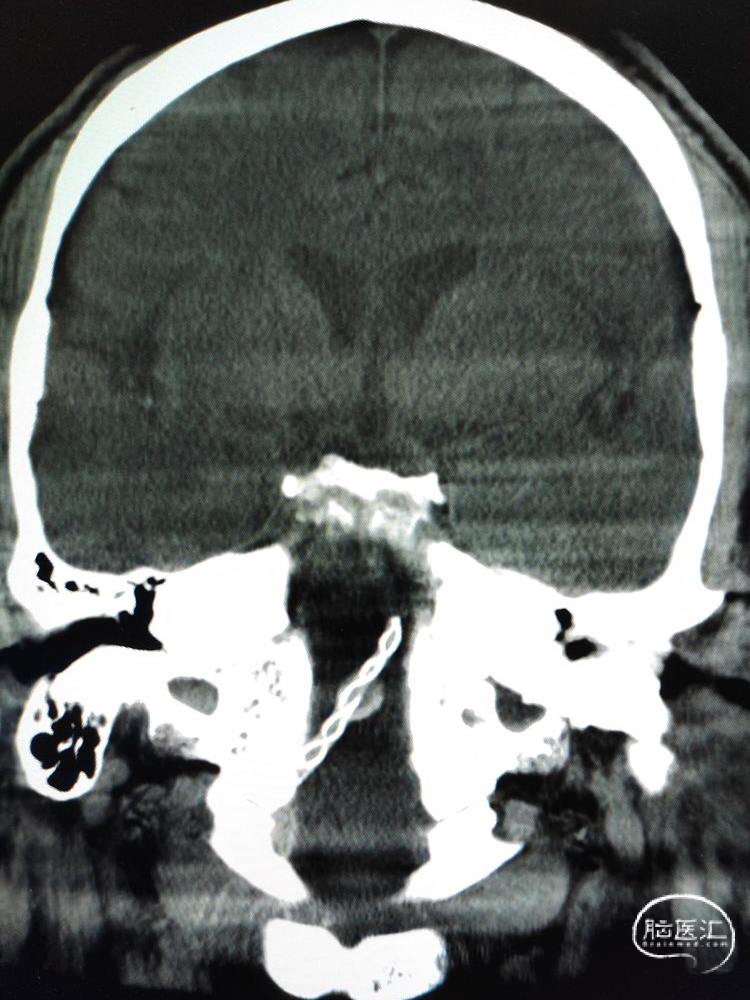

术前影像学检查:全脑血管造影检查提示右侧椎动脉V5段(颅内段)夹层动脉瘤。

动脉瘤大小约5.45mm×7.31mm,动脉瘤远端椎动脉汇合前管径约2.77mm,动脉瘤近端V4段管径约3.80mm,V5段全长约35mm,对侧椎动脉正常。

测量数据